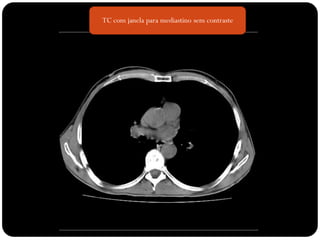

 TC janela de mediastino sem contraste

TC com janela para mediastino sem contraste